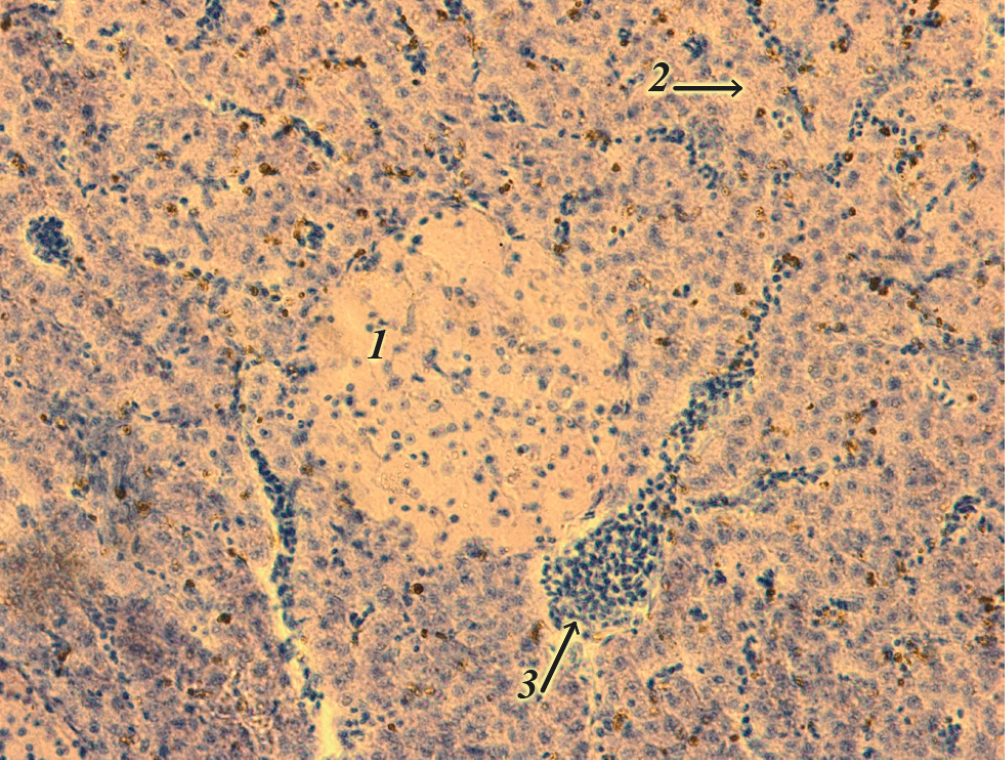

Рис. 3. Гепатоцеллюлярная аденома на фоне лейкоцитарной инфильтрации в печени обыкновенной кильки Clupeonella caspia. Ув. ×400. 1 – отдельный участок опухоли, 2 – отек паренхимы печени, 3 – вена

Кроме того, на срезе были отмечены мелкие кровоизлияния, что свидетельствовало о микроциркулярном расстройстве. У отдельных особей паренхима печени была отечна, не определялись границы клеток печени или их ядер. Серозная оболочка печени была разрушена. Балочная структура также не сохранена. На срезах печени других особей кильки регистрировали участки гепатоцеллюлярной аденомы, представляющие собой доброкачественные опухолевые образования, четко отделенные от окружающей паренхимы соединительной тканью (рис. 3).